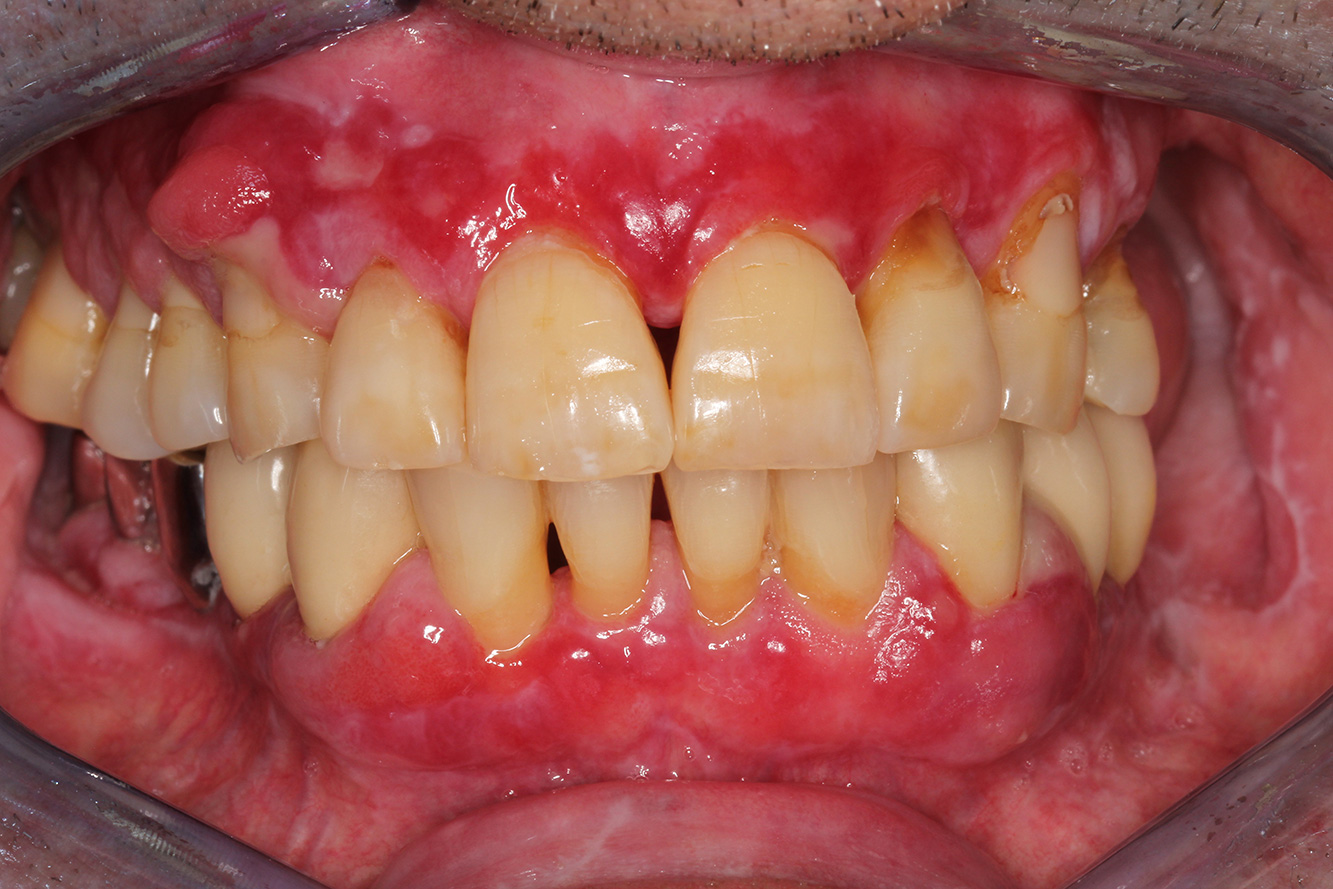

The healthy patient with pre-existing periodontal disease & peri-implantitis

A 52-year-old patient presents at a preventive care session. The patient has no systemic disease and is not taking any medication. He has had various dental treatments and also has two active carious lesions. In addition, the patient has four implants (2nd, 3rd and 4th quadrants). He is revealed to have early periodontal disease (stage IV, grade B). His periodontal condition is stable; a probing depth of Probing depths (ST) of 5 mm is only evident at the implant in region 36. Gingivitis is also identified. more